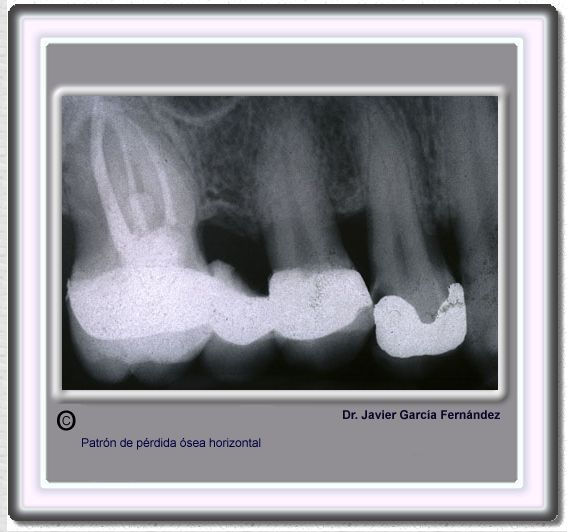

image 178